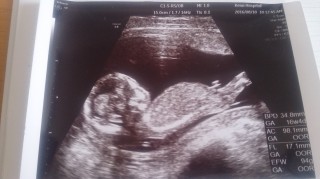

二人目です。 4Dを初めてやってもらいました♪ エイリアンみたい笑 頭3cm身長15cm 男の子かも?!